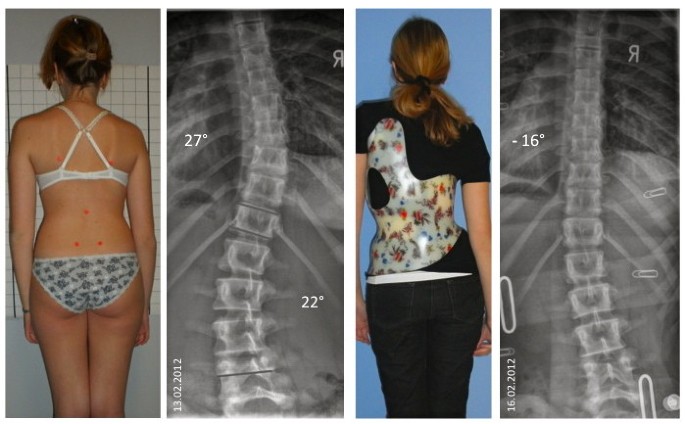

تابعت الدراسة مجموعة من الفتيات قبل البلوغ وأثناء بدايته، وجميعهن يعانين من جنف بسيط إلى متوسط ويستخدمن الحزام الطبي كعلاج.

هل يمكن منع تفاقم الانحناء خلال هذه المرحلة؟

نعم، في كثير من الحالات يساعد الالتزام بالحزام الطبي والمتابعة المنتظمة في تقليل احتمال التدهور.

الالتزام بمواعيد المتابعة الدورية وعدم تأجيلها.

التأكد من ارتداء الحزام الطبي حسب عدد الساعات الموصى بها.

مراقبة أي تغير واضح في مستوى الكتفين أو الخصر.

التحدث مع الطبيب حول مرحلة النمو الحالية ومدى خطورتها.

أحدث التقنيات العالمية: نعتمد على تقنيات حديثة مثل أجهزة التقييم الدقيقة وأحزمة التقويم المتقدمة مثل PioBrace.